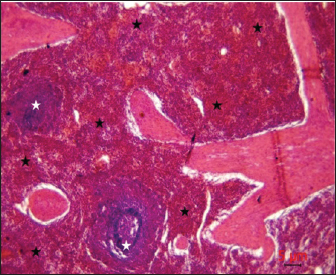

Post-mortem examination resultsPost-mortem examinations of the dead horses infected with M. haemofelis revealed signs of overall emaciation in the affected animals, paleness of internal organs (Fig. 5), and prominent splenomegaly. The liver, kidneys were enlarged; however, the heart showed white patches. Moreover, histopathological changes were characterized by different histopathological changes of eosinophilic degeneration of cardiac muscle fibers, accompanied by atrophy in some fibers, with bleeding between fibers, besides atrophic glomeruli, accompanied with the dilatation of renal tubules in the kidneys, as well as marked reduction in the proportion of white pulp of splenic tissue and degenerative changes in the cytoplasm of hepatocytes, accompanied by nuclear alterations characterized by loss of chromatin content in the hepatic tissue (Figs. 6–9).

Fig. 8. Histopathological evaluation of the spleen showed a marked reduction in the proportion of white pulp (white asterisk) relative to red pulp (black asterisk), H&E,4x. Scale bar=5µm.